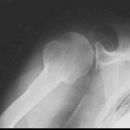

Schulter seitlich (Y-View)

Bei Luxation zusätzlich zur glenoidtangentialen Aufnahme problemlos durchführbar! Axiale Aufnahme schmerzbedingt meist nicht möglich.

Beurteilungskriterien

- Skapula bildet sich als Y ab

- Humeruskopf projiziert sich in das Glenoid? Luxation? Luxationsrichtung?

- Weite des subacromialen Raumes exakt nur in der 10 – 15° nach kaudal angulierten Aufnahme bestimmbar („Morrison, Outlet View“)! Normalerweise 1 - 1,5 cm, < 6 mm -> wohl pathologisch, Impingment wahrscheinlich

- Normvarianten: Os glenoidale (akzessorischer Ossikel kaudal des Glenoids), persistierende Akromion- oder Korakoidapophyse, entwicklungsbedingte Pfannenranddefekte

- Schulterluxationen:

- Anteriore Luxation (2) 95%= anteriore infraglenoidale Luxation, Kopf liegt vor Glenoid

- Posteriore Luxation (2) 3%: wird häufig übersehen! Kopf liegt hinter Glenoid, Hochstand des Humeruskopfes, fixierte Innenrotation des Humeruskopfes => atypische Projektion des Humeruskopfes: “ drumstick or bulb appearance“ (Birnenform), Muldenzeichen („trough line“), „rim sign“ in der ap bzw. glenoidtagentialen Aufnahme.

Zweite Ebene, z.B. transskapuläre Aufnahme zeigt die Richtung der Luxation. Cave. rein klinische Diagnose!

- Begleitverletzungen? (-> heute umfassend mit CT/MRT zu beurteilen)

- Tuberculum majus (15%)

- Pfannenrand

- Hill- Sachs Läsion = Dorsokraniale Humeruskopf-Impressionsfraktur (50%) (Aufnahme der 1. Wahl: Stryker oder CT)

- umgekehrte Hill-Sachs Läsion = anteromediale Impression nach hinterer Luxation

- Bankart-Läsion: Abriss des vorderen Labrum-Kapsel-Komplexes bzw. Abrissfraktur des vorderen unteren Glenoidrandes (-> CT-Athrographie, Arthro-MRT)